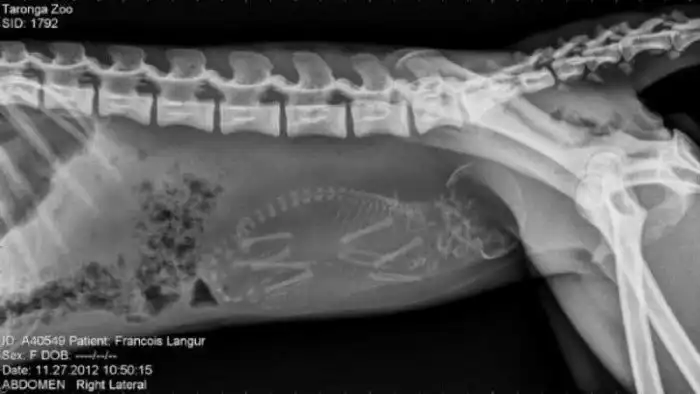

Специалисты, которые по долгу своей работы наблюдают животных, готовых принести потомство, поделились этими удивительными рентгеновскими и ультразвуковыми снимками.

13. Беременная обезьяна